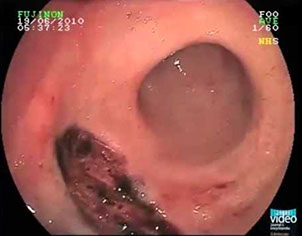

Colonic pseudopolyps in pt c intractable ulcerative colitis